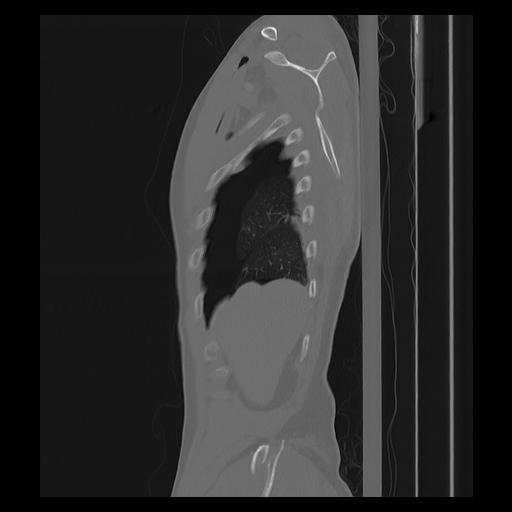

33 PULMON,CE,Sagittal,3.000,PULMON,Sagittal,